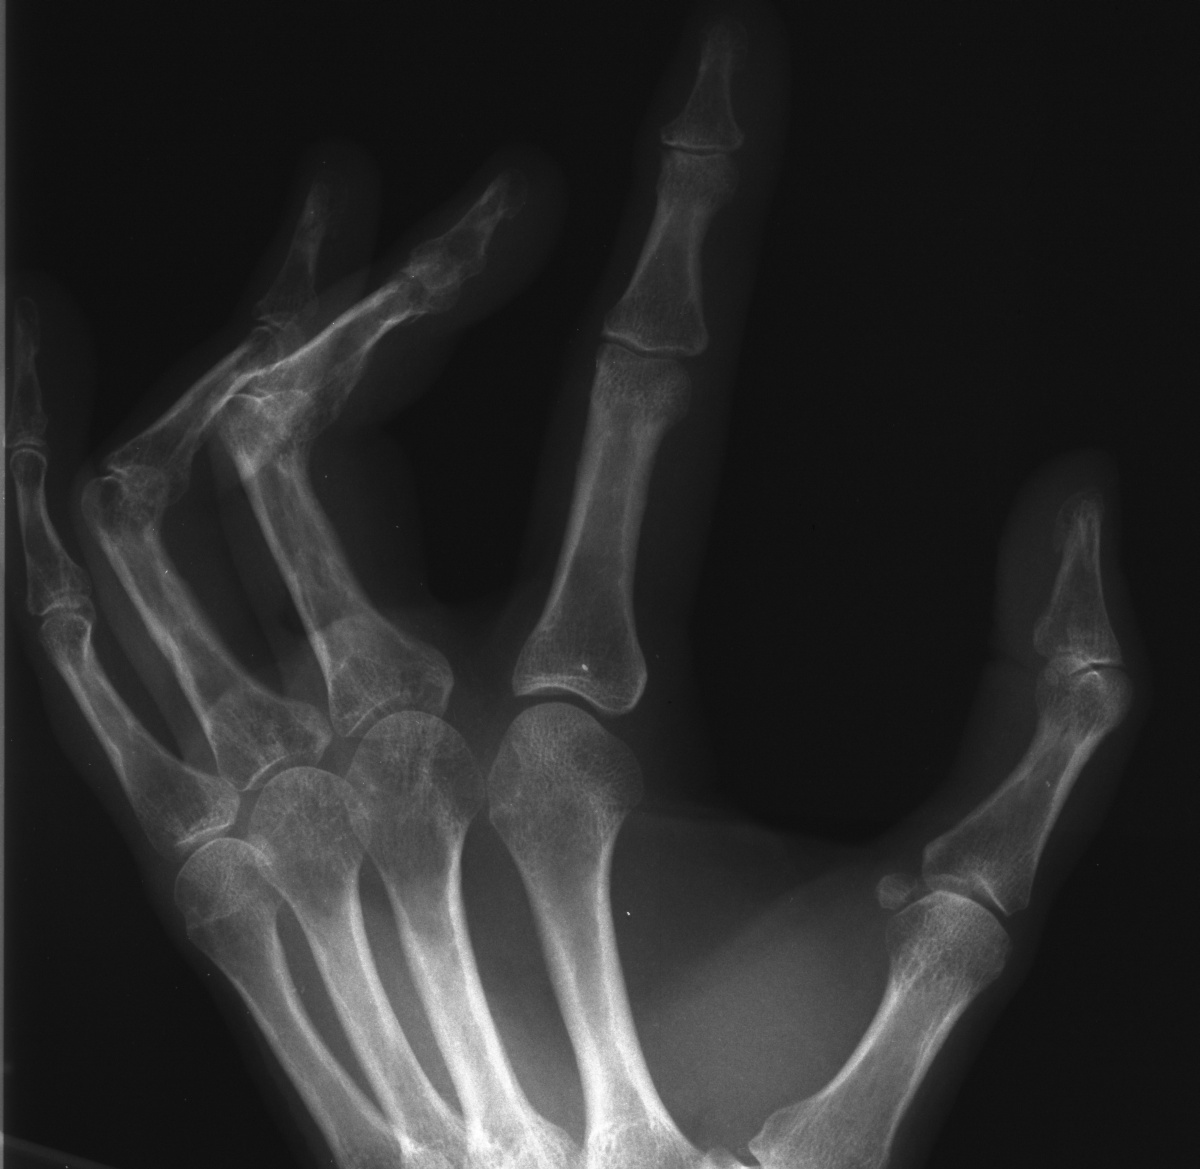

Standard AP radiographs fail to demonstrate PIP joint anatomy because of contractures.